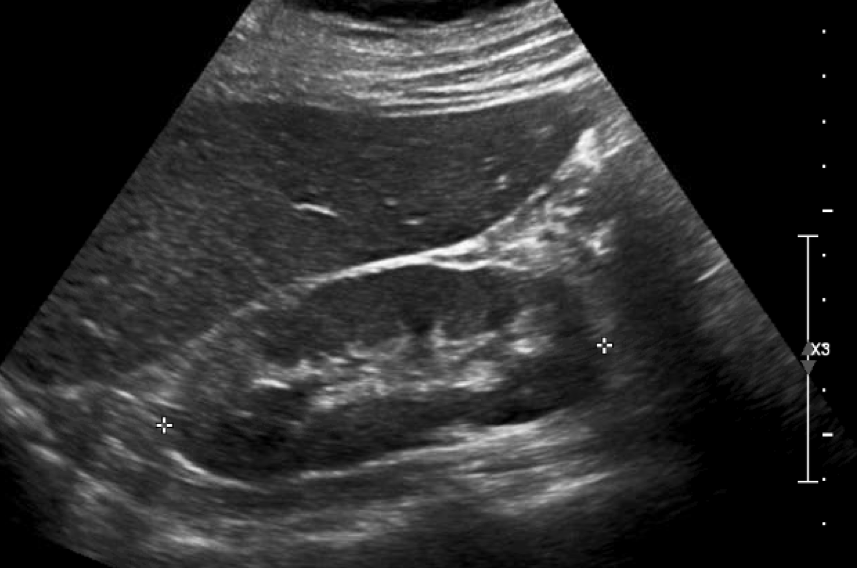

Kidney Ultrasound